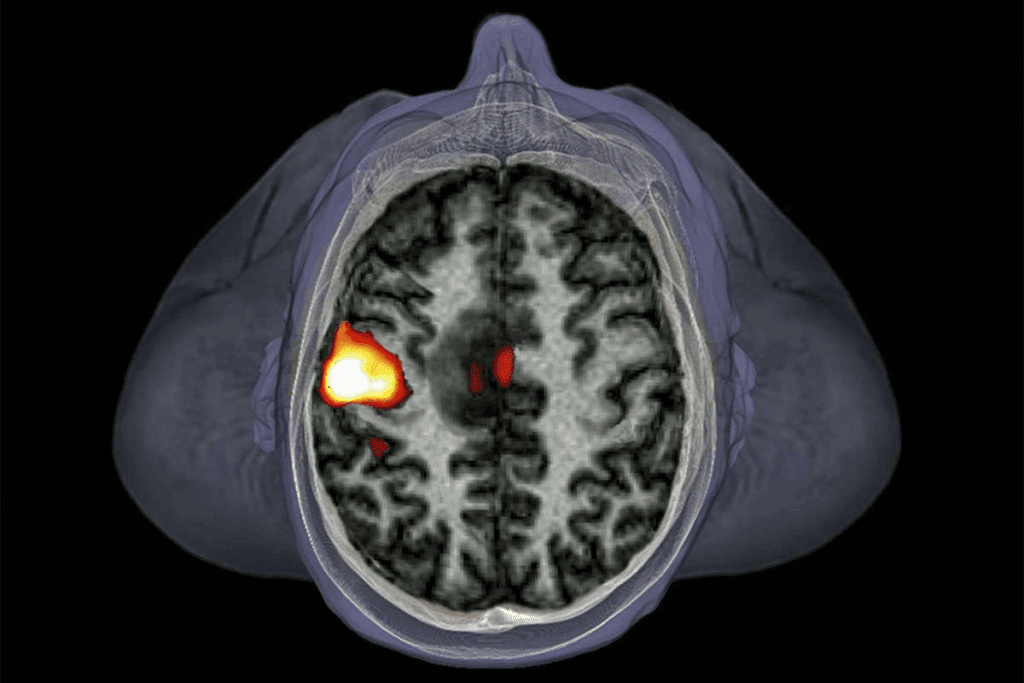

A brain aneurysm is a weak spot on an artery wall in the brain. It can cause serious health problems. We will look into how they form, what increases their risk, and the signs they may show.

Definition and Formation Process

A brain aneurysm happens when an artery wall in the brain weakens. This creates a bulge or sac-like structure. Weakness can come from genetics, high blood pressure, or atherosclerosis. The wall’s breakdown can lead to a rupture if not treated.